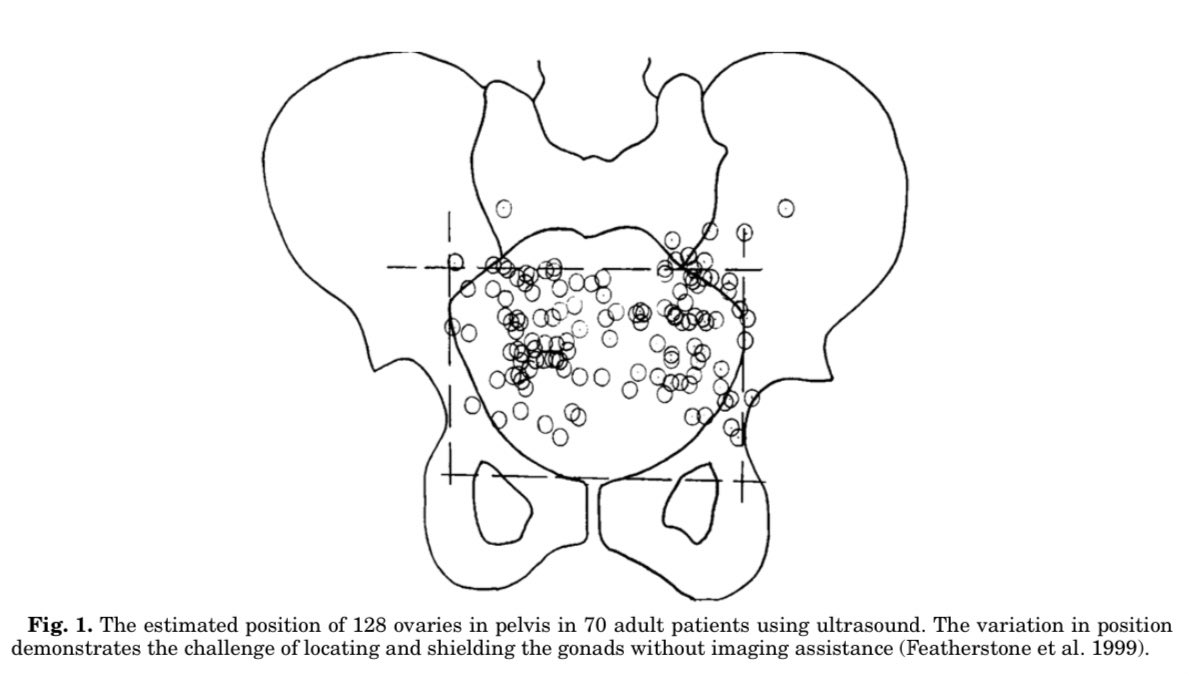

2️⃣حتى في حالة وضع الواقي في مكانه الصحيح فإن التشريح الطبيعي للأعضاء يختلف من مريض لآخر.

فهذا مثال للأماكن الطبيعية للمبايض.

فوضع الواقي في مكان صحيح لا يعني بالضرورة تغطية العضو الحساس.